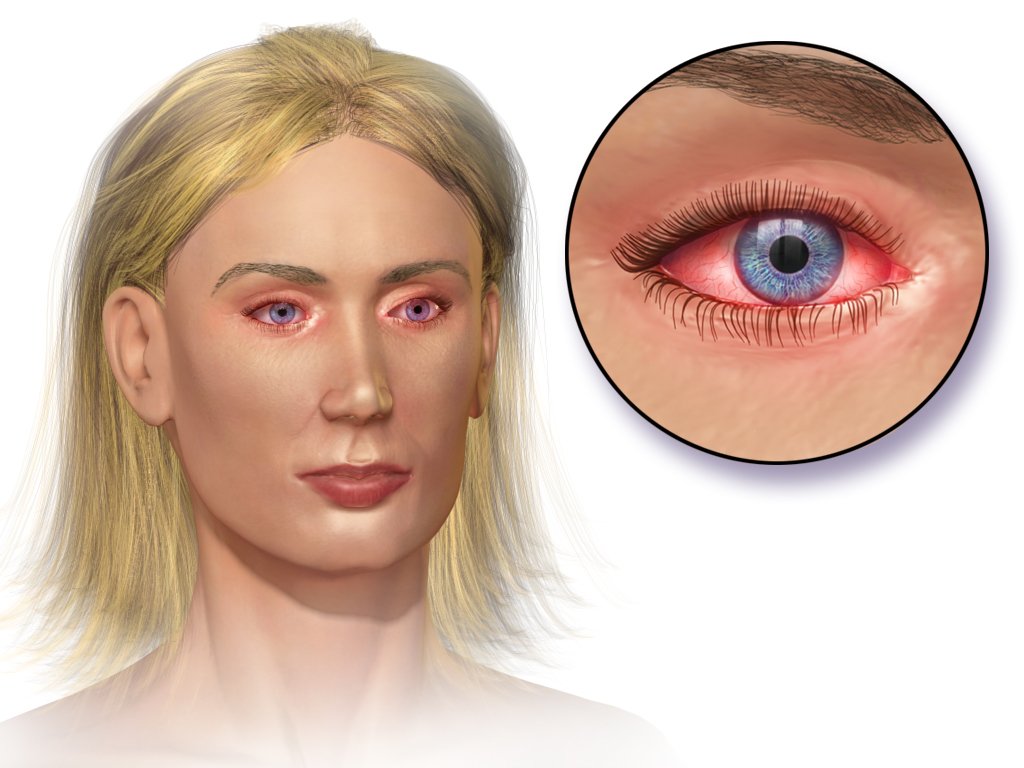

Lil Nas X Hospitalized: Facial Paralysis Sparks Concern

Lil Nas X Hospitalized After Experiencing Facial Paralysis Grammy-winning artist Lil Nas X is hospi...